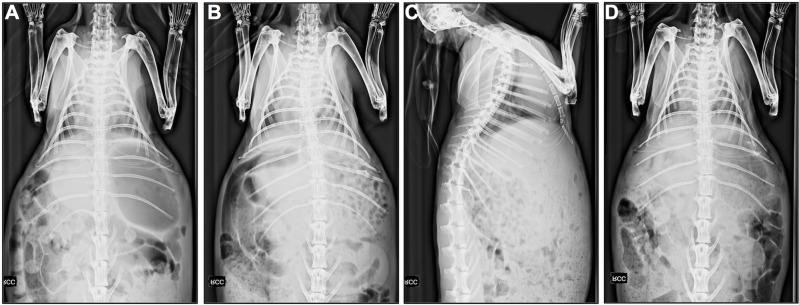

2.0x1.0 cm diaphragmatic defects were created in 6-weeks old New-Zealand white rabbits. We compared reconstruction with a purpose-designed cross-linked ACM (Matricel) to 4-layer non-cross-linked small intestinal submucosa (SIS) and a 1-layer synthetic Dual Mesh (Gore-Tex). Unoperated animals or animals undergoing primary closure (4/0 polyglecaprone) served as age-matched controls. 60 (n = 25) resp. 90 (n = 17) days later, animals underwent chest x-ray and obduction for gross examination of explants, scoring of adhesion and inflammatory response. Also, uniaxial tensiometry was done, comparing explants to contralateral native diaphragmatic tissue.

Overall weight nearly doubled from 1,554±242 g at surgery to 2,837±265 g at obduction (+84%). X-rays did show rare elevation of the left diaphragm (SIS = 1, Gore-Tex = 1, unoperated control = 1), but no herniation of abdominal organs. 56% of SIS and 10% of Matricel patches degraded with visceral bulging in four (SIS = 3, Matricel = 1). Adhesion scores were limited: 0.5 (Matricel) to 1 (SIS, Gore-Tex) to the left lung (p = 0.008) and 2.5 (Gore-Tex), 3 (SIS) and 4 (Matricel) to the liver (p<0.0001). Tensiometry revealed a reduced bursting strength but normal compliance for SIS. Compliance was reduced in Matricel and Gore-Tex (p<0.01). Inflammatory response was characterized by a more polymorphonuclear cell (SIS) resp. macrophage (Matricel) type of infiltrate (p<0.05). Fibrosis was similar for all groups, except there was less mature collagen deposited to Gore-Tex implants (p<0.05).